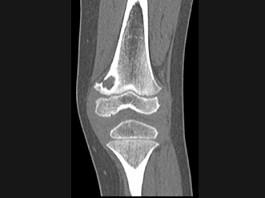

问题 男,12岁,大腿下部间歇性疼痛,劳累后加重,结合图像,最可能的诊断是 ( )

选项 A、邻皮质软骨瘤 B、非骨化性纤维瘤 C、干骺端结核 D、骨样骨瘤 E、纤维性骨皮质缺损

答案 E